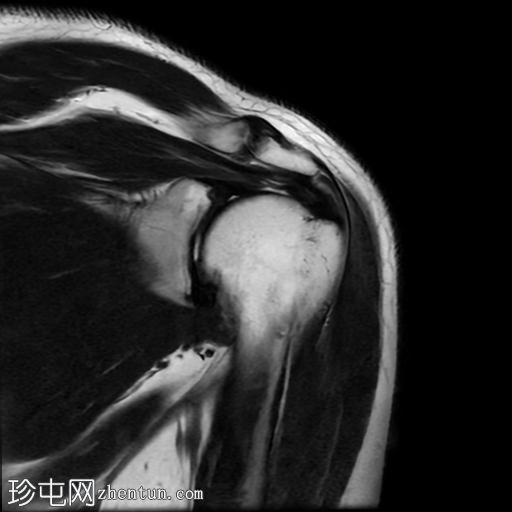

T2加权像

冠状位

冈上肌腱中后部关键区及肌腱止点纤维可见一低信号椭圆形病灶,大小约5 x 8 x 16 mm,提示钙化性肌腱炎。

肩锁关节轻度关节囊肥厚及退行性改变。

肩峰类型:II型

肩袖钙化性肌腱炎是一种自限性疾病,由羟基磷灰石钙沉积引起,最常见于冈上肌腱。